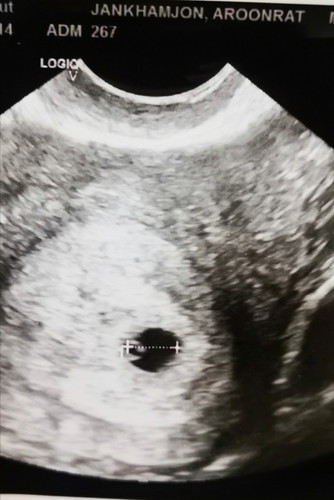

ถ้านับจากปจด.จะ6wแต่ไปซาวด์คุณหมอบอกว่า5wค่ะ เห็นถุงตั้งครรภ์ ถุงไข่แดง แต่ยังไม่เจอตัวเด็ก เลยกลับมาดูแผ่นฟิล์มริมๆถุงตั้งครรภ์เหมือนเห็นอะไรงอๆขาวๆ 5555หรือเราคิดไปเองว่านั่นคือตัวอ่อน

ซูมตามเลยค่ะ 555